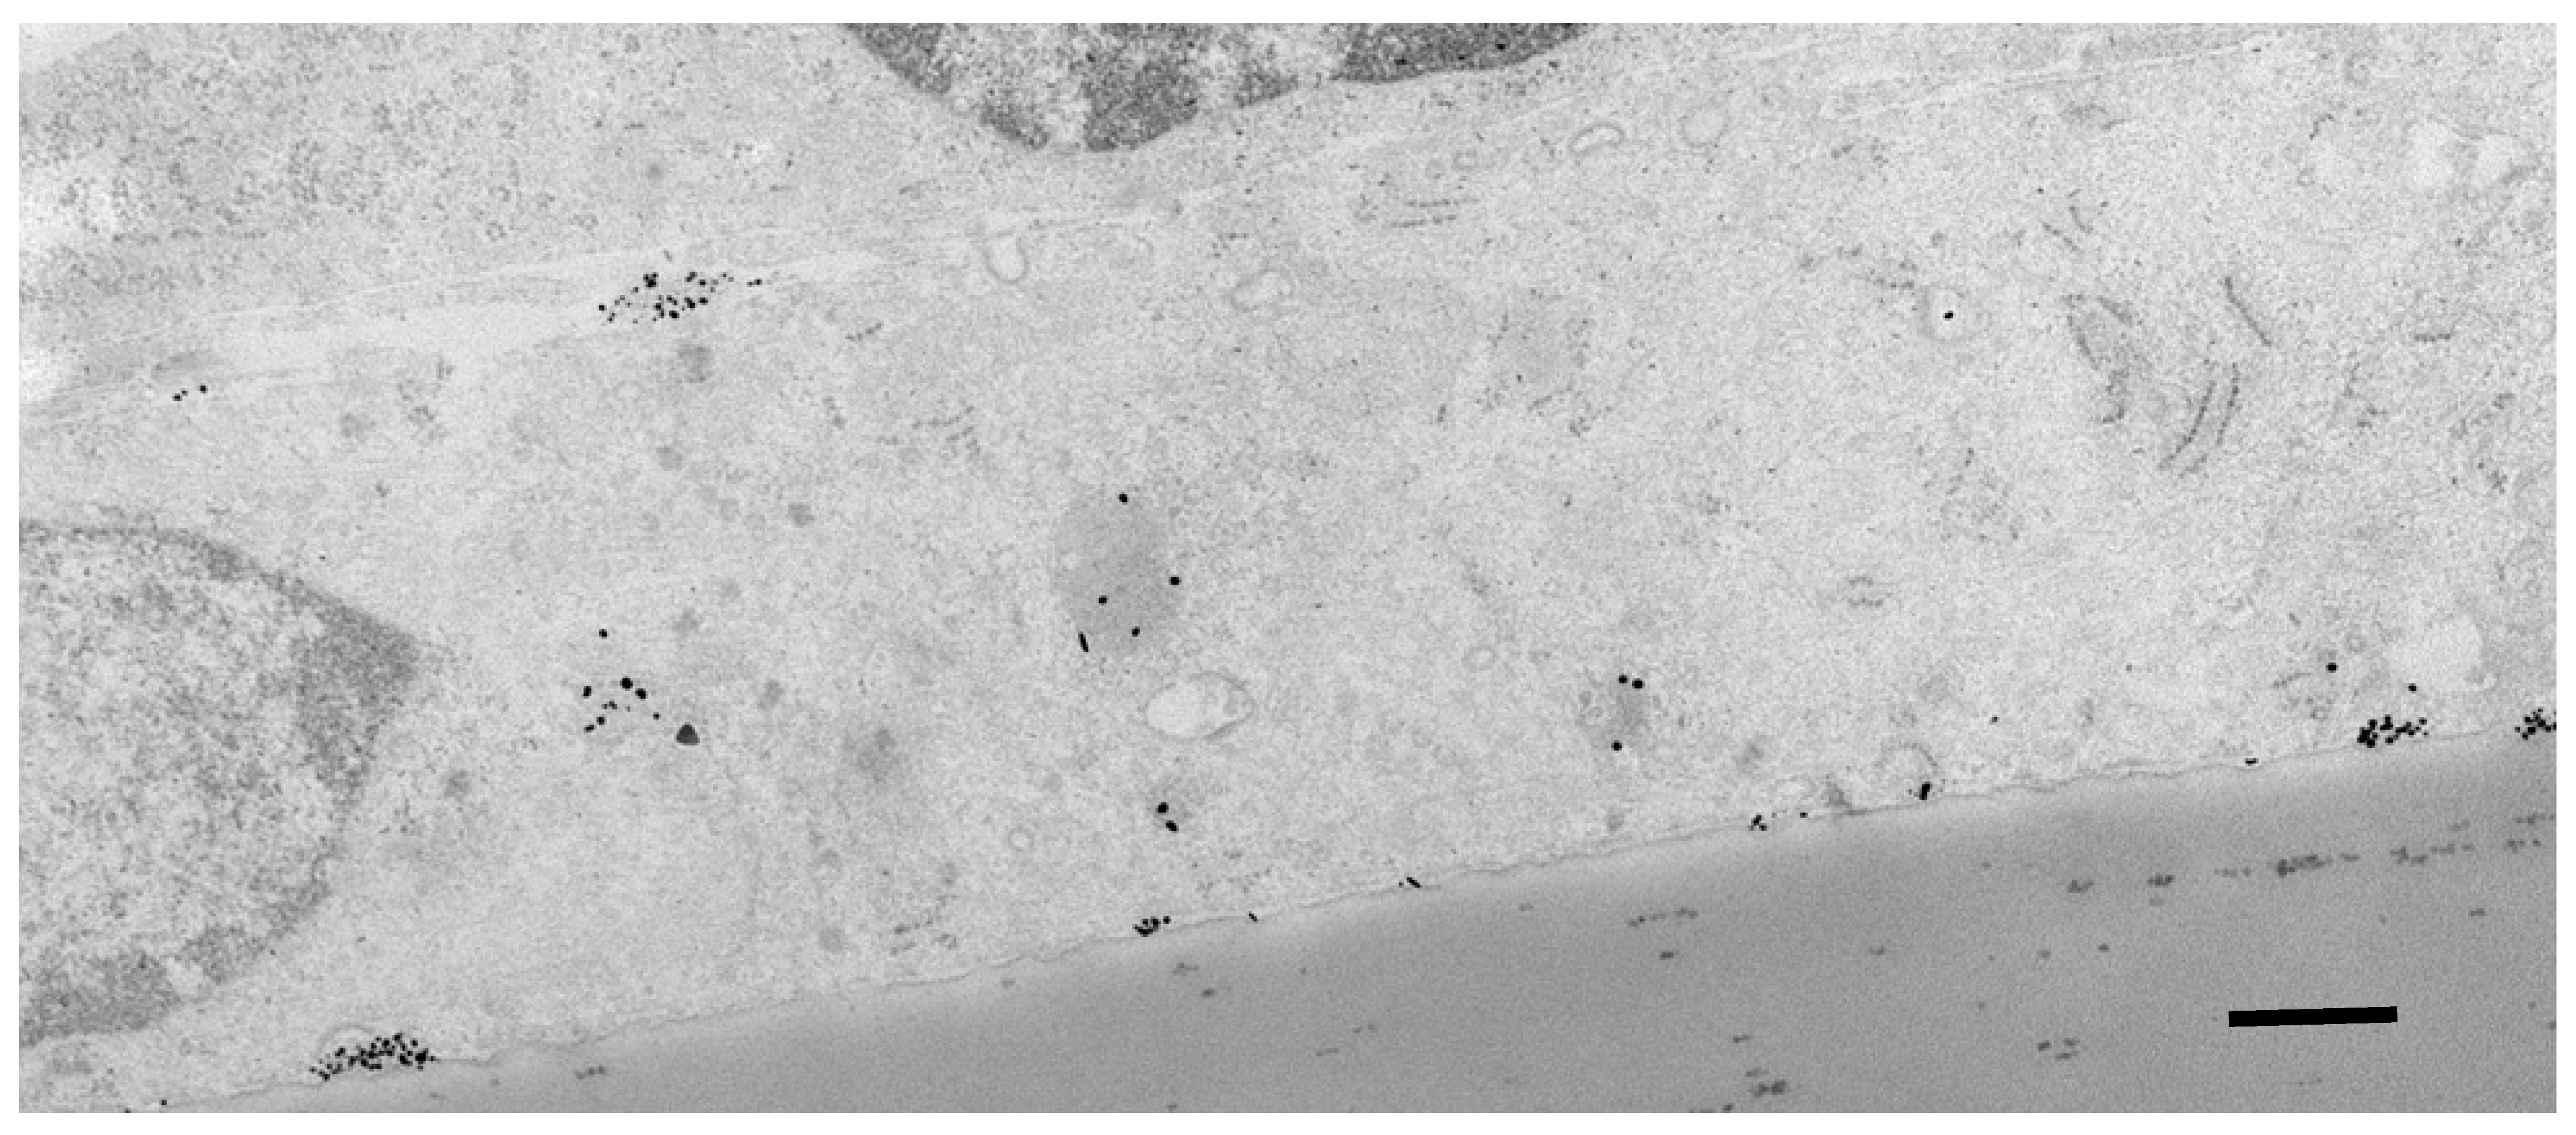

- Fatima, N.; Gromnicova, R.; Loughlin, J.; Sharrack, B.; Male, D.K. Gold nanocarriers for transport of oligonucleotides across brain endothelial cells. PLoS ONE 2020, 15, e023661. [Google Scholar] [CrossRef]

- Fatima, N.; Akcan, U.; Kaya, M.; Gromnicova, R.; Loughlin, J.; Sharrack, B.; Male, D. Tissue distribution and cellular localization of gold nanocarriers with bound oligonucleotides. Nanomedicine 2021, 16, 709–720. [Google Scholar] [CrossRef]